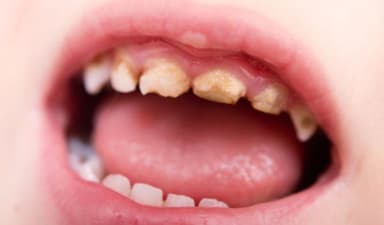

2.2. Răng có những vết đen hoặc xuất hiện lỗ li ti

Sâu răng ban đầu thường biểu hiện bằng các đốm trắng mờ, sau đó chuyển sang màu nâu hoặc đen. Một số trẻ còn xuất hiện lỗ nhỏ trên bề mặt răng hàm – đây là dấu hiệu men răng đã bị phá hủy, cần đưa trẻ đi khám nha sĩ ngay để tránh tình trạng sâu răng tiến triển.